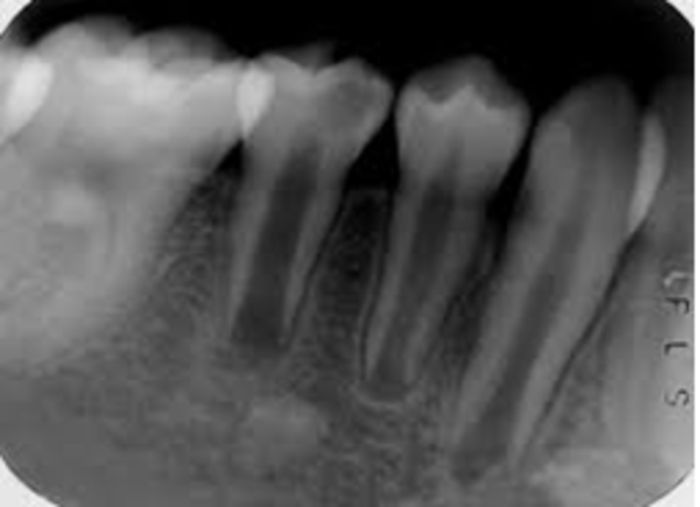

近中邻 牙合 面大面积龋坏,无叩痛,牙髓活力正常,x:根尖孔未完全闭合

完全形成和成熟;其主要特点是牙根短,根管粗大,根尖孔呈喇叭口状(图1)

图3-39 根尖孔解剖随着年龄的变化,根尖区牙体组织不断沉积,根尖孔的